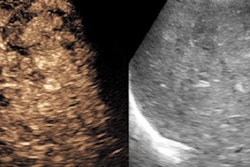

The U.S. Preventive Services Task Force (USPSTF) today issued a final rule rejecting the screening of asymptomatic patients for thyroid cancer using palpation or ultrasound.

The decision comes as no surprise, given that the announcement largely hews to a draft recommendation the group issued in November. The USPSTF stated that there isn't much benefit to detecting low-risk thyroid cancer before patients are symptomatic. It found that screening carried with it the risk of overdiagnosis by finding tumors that might never pose a risk to individuals in their lifetimes -- a commonplace occurrence given the slow-growing nature of most thyroid cancers.

However, a related paper noted that the recent increase in thyroid cancer incidence may not be solely due to overdiagnosis. Learn more by clicking here, or visit our Ultrasound Community at ultrasound.auntminnie.com.